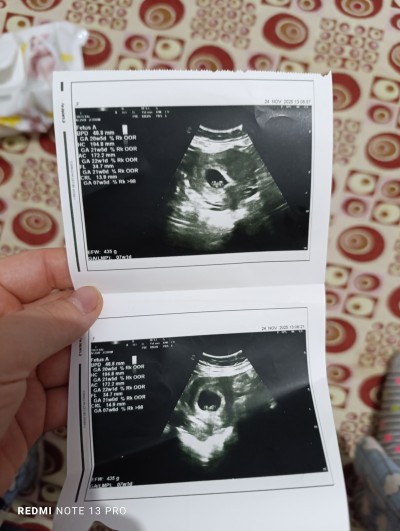

image

yorumlari bekliyorum

Gebelik haftası 7+6